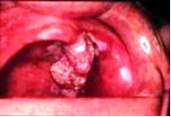

Karcinom sluznice usta

Ovaj karcinom je najčešći maligni tumor sluznice usta. Makroskopski se

razlikuju vegetantna i ulcerozna forma.

Vegetantni ili egzofitični oblik raste iznad nivoa površine

okolne sluznice. Širokom bazom je pripojen za podlogu koju infiltriše

i prodire u dublje slojeve. U toku daljeg rasta dolazi do pojave ulceracija.

Podseća na karfiol, što je naročito izraženo kod zrelijih formi gde usled

orožavanja dolazi do pojave beličastih naslaga. Promena je u početku potpuno

bezbolna, na palpacije izražena induracija.

Ulceroznu formu karcinoma imamo uvek kada dolazi do bržeg

rasta parenhima nego strome tumora. Usled nekroze dolazi do pojave ulkusa.

Ivice su neravne, podrivene, nešto iznad nivoa okolne sluznice, dno ulceracije

je prekriveno sivkastim ili žućkastim fibrinskim naslagama. Palpacijski

je izražena induracija u mnogo jačem stepenu nego kod vegetantne forme.

Kod uznapredovalog stadijuma ulkus se povećava, a ivice ulkusa se pomeraju

prema periferiji i dubini. Imaju relativno lošu prognozu jer vrlo brzo

metastaziraju u regionalne limfne žlezde submandibularne i submentalne,

a kasnije zahvataju limfne žlezde vrata. Metastazno uvećane limfne žlezde

su u početku okruglasti, čvrsti, bezbolni čvorovi, u početku pokretni,

a kasnije fiksirani za okolinu, a u terminlanoj fazi mogu kolikvirati

i egzulcerisati. Na kraju prodorom u krvne i limfne sudove mogu dati udaljene

metastaze. Stepen maligniteta karcinoma sluznice usta se povećava idući

iz gornjih prema donjim partijama usne šupljine, a isto tako i od napred

prema nazad.